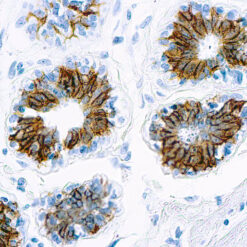

This MAb recognizes human 17-26kDa protein, which is identified as cytokine TNF-α (Tumor Necrosis Factor-alpha). Monomeric human TNF-α is a 157 amino acid protein (non-glycosylated) with a reported molecular weight of 17 kDa and can be expressed as a free molecule, also TNF-α is generated as a precursor form called transmembrane TNF-α can be expressed as a cell surface type II polypeptide consisting of 233 amino acid residues molecular weight 26 kDa. TNF-α is an important cell-signaling component of the immune system. It is a protein secreted by LPS stimulated macrophages, and causes tumor necrosis when injected into tumor bearing mice. TNF-α is currently being evaluated in treatment of certain cancers and AIDS Related Complex.

| Positive Control Tissue | Colon, Histiocytoma, Pancreas |